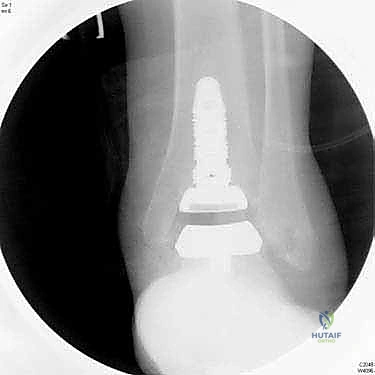

5. تركيب المكونات المفصلية

يتم تثبيت القاعدة المعدنية السفلية على عظمة القعب (Talus). ثم يتم إدخال قطعة بلاستيكية عالية التحمل (بولي إيثيلين) بين القطعتين المعدنيتين. هذه القطعة البلاستيكية تعمل كغضروف صناعي، مما يسمح للمفصل بالانزلاق بحرية وسلاسة تامة.

6. التحقق والإغلاق

يتم فحص المدى الحركي للكاحل الجديد وثباته تحت جهاز الأشعة السينية (Fluoroscopy) داخل غرفة العمليات للتأكد من المحاذاة المثالية بنسبة 100%. بعد ذلك، يتم إغلاق الشق الجراحي بغرز تجميلية، ووضع جبيرة ناعمة أو حذاء طبي واقٍ.